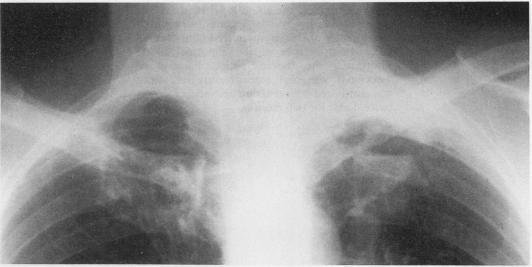

Pancoast's syndrome due to Pseudomonas aeruginosa infection of the lung apex.

A case of Pancoast's syndrome was caused by Pseudomonas aeruginosa infection of the lung apex. The infection extended to extrapleural structures of the thoracic inlet.